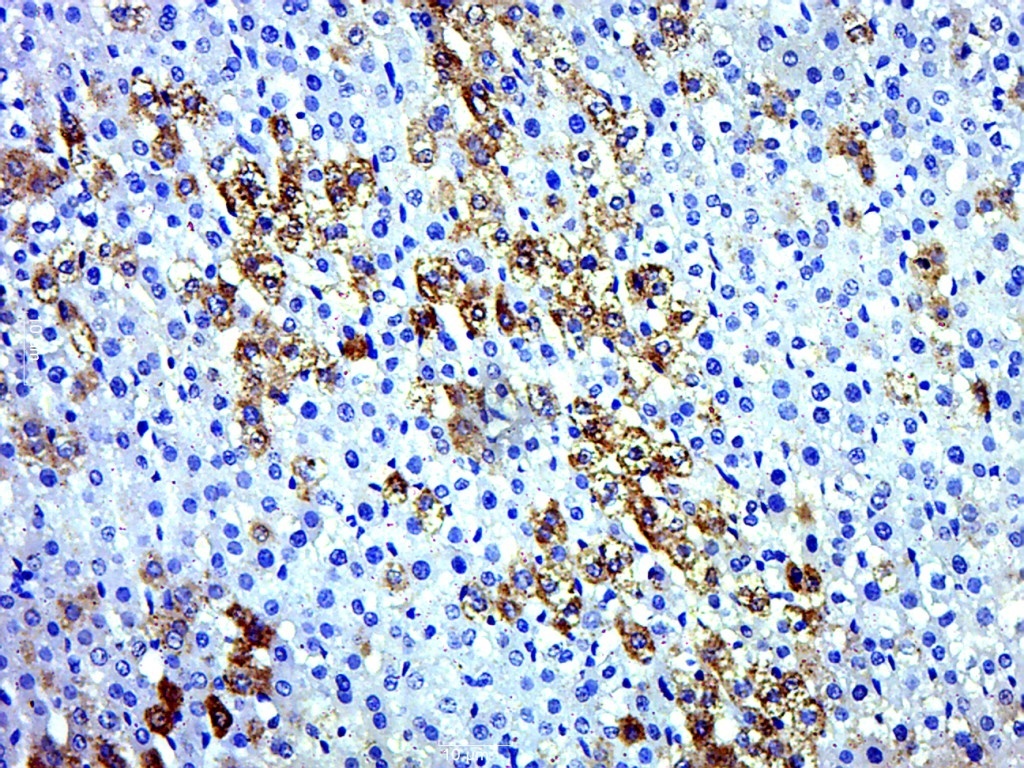

| 英文名称 | ERp57 Rabbit pAb |

| 中文名称 | 内质网蛋白57抗体 |

| 产品应用 | WB=1:500-2000, IHC-P=1:100-500, IHC-F=1:100-500, IF=1:100-500 Not yet tested in other applications. |

| 交叉反应 | Human, Mouse, Rat (Chicken, Rabbit) |

| {IHC-P} | {1:100-500} |

| 背景资料 | This gene encodes a protein of the endoplasmic reticulum that interacts with lectin chaperones calreticulin and calnexin to modulate folding of newly synthesized glycoproteins. The protein was once thought to be a phospholipase; however, it has been demonstrated that the protein actually has protein disulfide isomerase activity. It is thought that complexes of lectins and this protein mediate protein folding by promoting formation of disulfide bonds in their glycoprotein substrates. [provided by RefSeq, Jul 2008] |